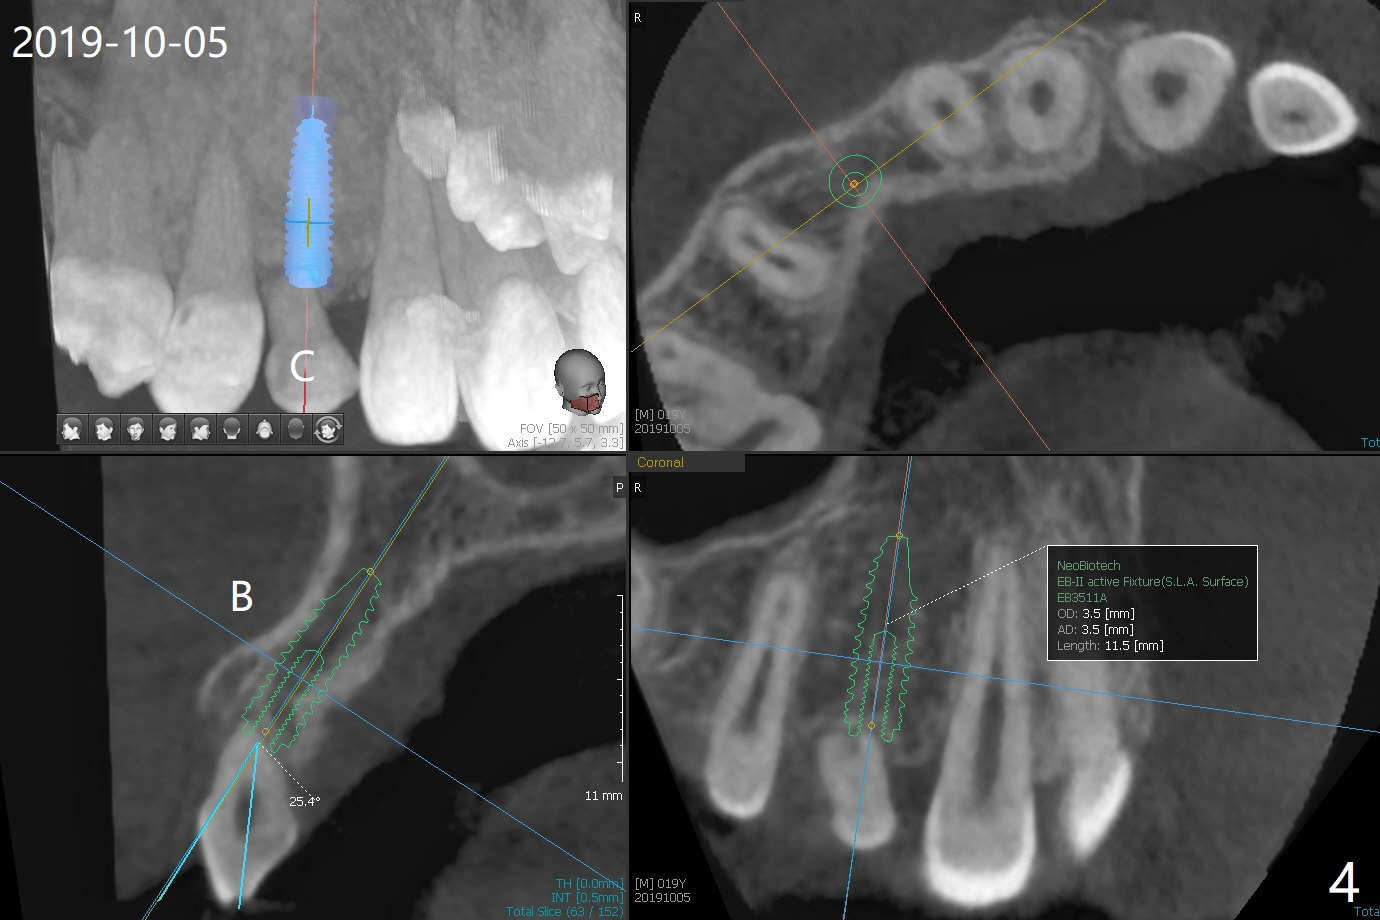

A 20-year-old man requests implant for the loose upper left deciduous canine. Pre-orthodontic panoramus shows 3 implants are needed (Fig.1). Post-ortho PAs indicate root resorption of the upper right deciduous canine as well (Fig.2,3). To reduce radiation, 5x5 cm CBCT is taken for the anterior maxilla, the 1st implant to be placed at #11 in the Thanksgiving this year, while the 2nd one at #6 early next January (Fig.4,5). 1-piece implants may simplify treatment.